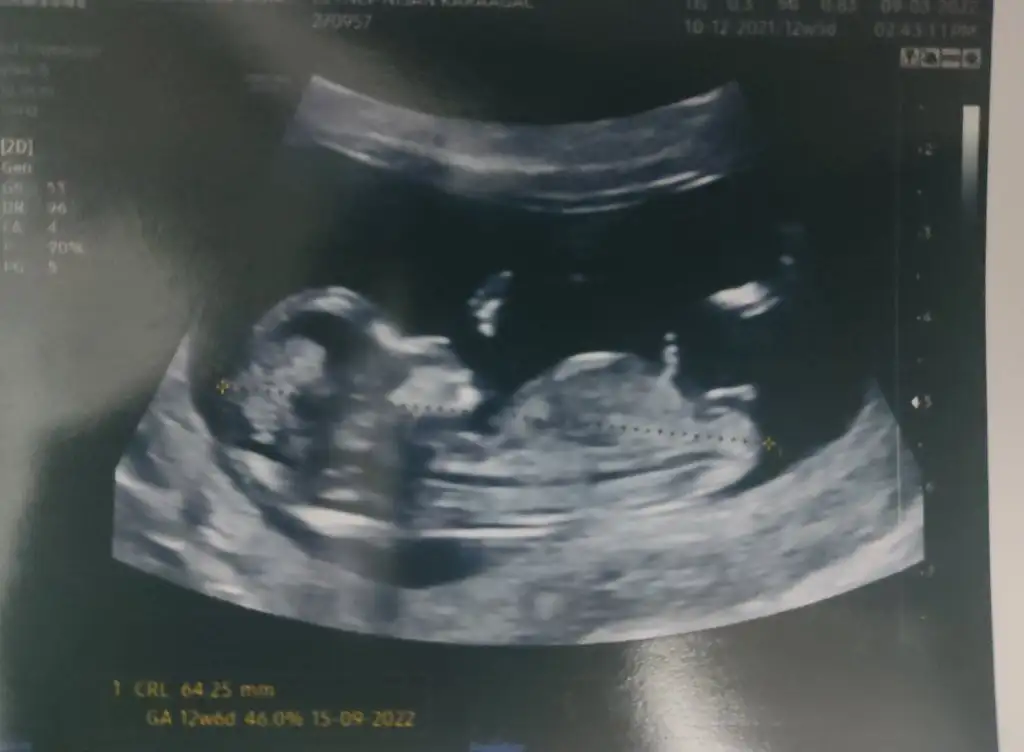

Göbek kordonunun altındakini pipiye benzettim inşallah öyledir canımMerhabalar.rica etsem benimde yorumlarmisiniz12+6 dayım şuan

Kız bebek nuba göre genital çıkıntı paralel gözüküyor, yöntem denemişmiydimiz erkke bebek içinMerhabalar.rica etsem benimde yorumlarmisiniz12+6 dayım şuan

Kız bebek nuba göre genital çıkıntı paralel gözüküyor, yöntem denemişmiydimiz erkkeMerhabalar.rica etsem benimde yorumlarmisiniz12+6 dayım şuan

Kafa yapısı ı ve nubu kesinlikle erkek gözüküyor,Merhaba benim 2 kızım var şuan 3.hamileyim cinsiyet tahmini yapabilir misiniz 12+1 usg resmimizi atayım kemik yapısı kafa yapısı nün teorisi anlayan varsa yorumlarınızı bekliyorum, sat 1/12/2021 Doğum tarihim 07/03/1990 eşimin doğum tarihi 07/12/1985